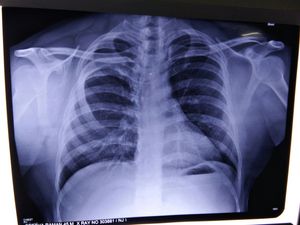

###:Look very carefully to find the abnormality.... ### if clue needed comment below...

Bony deformity.... Closely look at the ribs...

Dislocated rib?

I can see the rib on right side is not normal. Can u tell the answer?

Offset clavicle has something to do With it? Maybe

Clavicle is fine man....